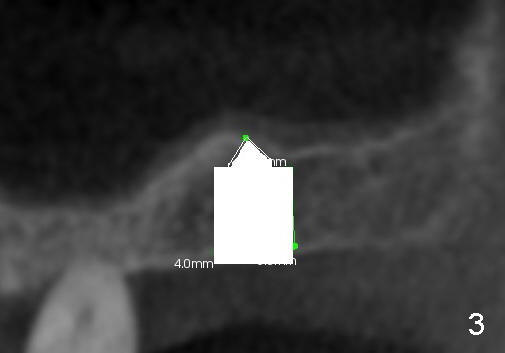

Fig.1 shows the sagittal section of the upper right posterior quadrant (3: #3 palatal root, 2: edentulous area to receive implant; S: sinus). The bone height is 5.8 mm. If the trephine bur with 4 mm outer diameter) does not engage into the bone easily, a 2.0 mm pilot drill is used to create initial osteotomy short of sinus floor (~4 mm deep). Osteotomy is increased by sequentially using 2.5, 3.0, 3.5 and 4.0 mm reamers (Fig.3). Bone shaving is saved. The last 1-2 mm of osteotomy (i.e., sinus floor) is prepared using 4 mm trephine bur (Fig.4 red lines). A flat end osteotome (4 mm in diameter, Bicon comprehensive kit) or tap is used to push the sinus floor upward gently and slowly (Fig.5 arrow). Use a small curet to separate the sinus membrane off the sinus floor lateral to the osteotomy. Put the saved autogenous bone graft back to the osteotomy. Push it upward with Bicon bone condenser. When an implant is placed (Fig.6 pink outline, e.g., 6x11 mm), the top is covered by the vital bone, whereas the side by the harvested bone (*, although the latter loses direct blood supply).